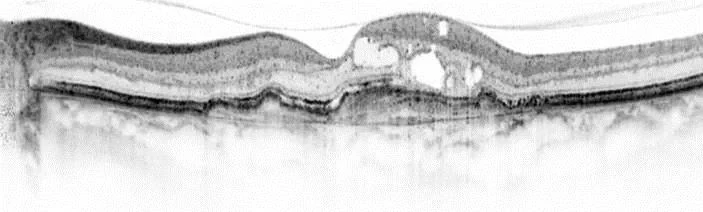

Optische Kohärenztomographie

Optische Kohärenztomographie - bei neovaskulärer altersabhäniger Makuladegeneration. © Quelle: Universitäts-Augenklinik Bonn

Dr. Maximilian Pfau und Leon von der Emde von der Universitäts-Augenklinik Bonn haben nun einen Algorithmus mit künstlicher Intelligenz (KI) entwickelt, der es erlaubt, automatisch die Sehfunktion vorherzusagen. Als Grundlage verwenden sie hierzu die Aufnahmen der optischen Kohärenztomographie. Mit diesem Routineverfahren lässt sich innerhalb kürzester Zeit der zentrale Augenhintergrund in hochaufgelösten Schichten abbilden. Der innovative KI-Ansatz erlaubt nun anhand dieser Aufnahmen die Funktion von Stäbchen- und Zapfen-Photorezeptoren zu kartieren, die jeweils verantwortlich für das Nacht- beziehungsweise Tagsehen sind. „Dieser Ansatz ermöglicht uns, den Patienten zeitaufwendige funktionelle Tests zu ersparen und dennoch die Funktion der Netzhaut genau einzuschätzen“, sagt Pfau.

Zudem fanden die Bonner Forscher heraus, dass Läsionen bei AMD sich ganz unterschiedlich auf das Nachtsehen- und Tagsehen auswirken können, „Interessanterweise beeinflusst ein Netzhautverdickung bei Makulaödem die Funktion von Stäbchen-Photorezeptoren, die verantwortlich für Nachtsehen sind, deutlich ausgeprägter als die Funktion von Zapfen-Photorezeptoren. Die Wirksamkeit neuer Therapieansätze lässt sich also aufgrund solcher Unterschiede der Stäbchen- und Zapfen-Photorezeptorfunktion beurteilen“, so Pfau. Die jetzt publizierte Arbeit stellt hierzu eine wichtige Grundlage dar.